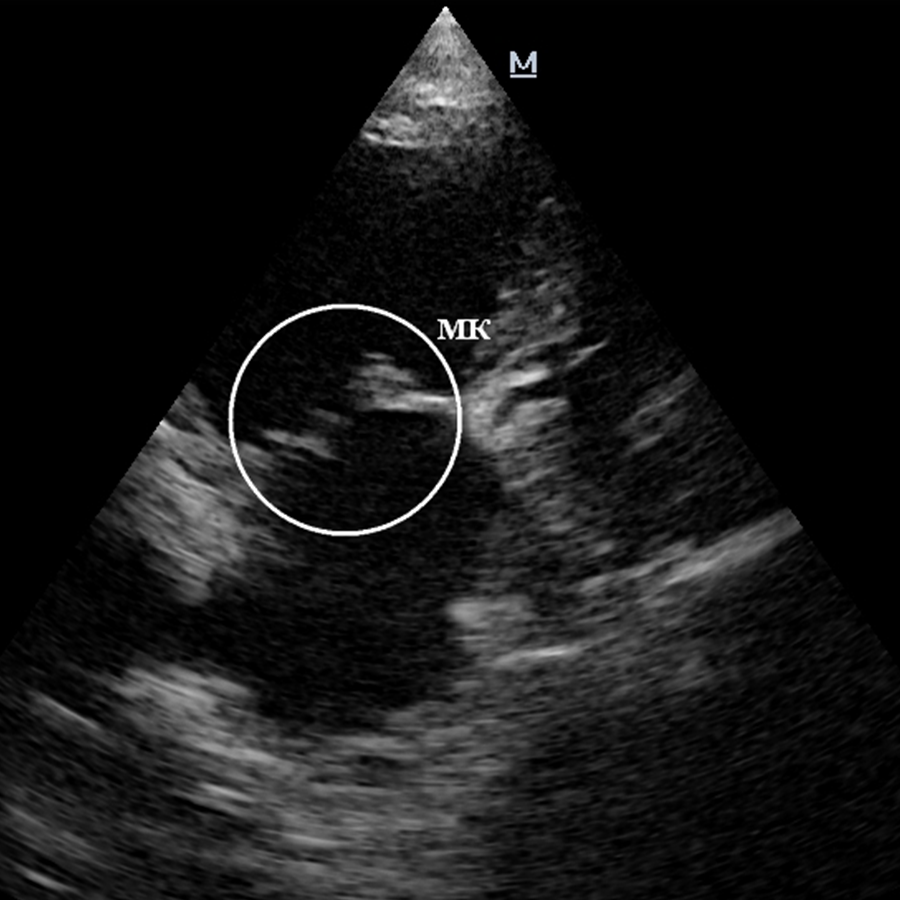

Окончательный диагноз ставится на основании ультразвукового исследования сердца (ЭХО КГ).

Митральный клапан расположен между левым желудочком и предсердием. Его функция – при сокращении сердца смыкаться и препятствовать обратному току крови. С возрастом створки митрального клапана утолщаются и деформируются, перестают плотно закрываться в момент сокращения сердца и начинают пропускать кровь, в результате чего возникает обратный ток крови в предсердие. Часть ударного объема крови во время систолы попадает обратно в левое предсердие, а сердечный выброс крови в аорту снижается. При длительном течении болезни левое предсердие растягивается и в нем повышается давление. Какое-то время сердечная мышца может компенсировать это процесс, но в дальнейшем начинается рост давления и в левом желудочке и он тоже растягивается. Следствием повышенного давления в левом предсердии является повышение давления в легочных венах, что приводит к левосторонней сердечной недостаточности. Итог описанных процессов – развитие застоя крови в малом круге кровообращения и отек легких. На последних стадиях развития болезни может пострадать и правая половина сердца. В дальнейшем это приведет к легочной гипертензии, либо к скоплению жидкости в брюшной полости (асциту).